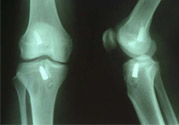

1、部分?jǐn)嗔眩宏P(guān)節(jié)內(nèi)無(wú)積血,外翻位X線片顯示內(nèi)側(cè)關(guān)節(jié)間隙不大,可做局部封閉、彈性繃帶加壓包扎,早期鍛煉股四頭肌或用踝上長(zhǎng)腿石膏托固定于膝內(nèi)翻和稍屈位3—4周,石膏完全干后可開(kāi)始股四頭肌鍛煉和下地行走。

2、完全斷裂:原則上應(yīng)行手術(shù)治療如韌帶斷裂,可直接縫合;如骨附著處撕脫,可用鋼絲貫穿法固定或直接縫合于骨膜及軟組織上。如有撕脫骨片,則用鋼絲或螺絲釘固定。如合并半月軟骨損傷,應(yīng)予以切除。合并前膝交叉韌帶損傷者,應(yīng)先修補(bǔ)。術(shù)后石膏固定4—6周。

4、膝交叉韌帶損傷:前交叉韌帶合并脛骨棘撕脫骨折者,可用膝過(guò)伸和后推脛骨使之復(fù)位,用長(zhǎng)腿石膏固定4—6周。對(duì)于未能復(fù)位者,應(yīng)及時(shí)手術(shù)修補(bǔ)。將骨折片用鋼絲固定。單純韌帶斷裂者,用石膏固定。對(duì)陳舊性損傷,以保守治療為主,經(jīng)鍛煉后,關(guān)節(jié)仍不穩(wěn)定,亦可考慮手術(shù)修補(bǔ)。后交叉韌帶可不修補(bǔ)。